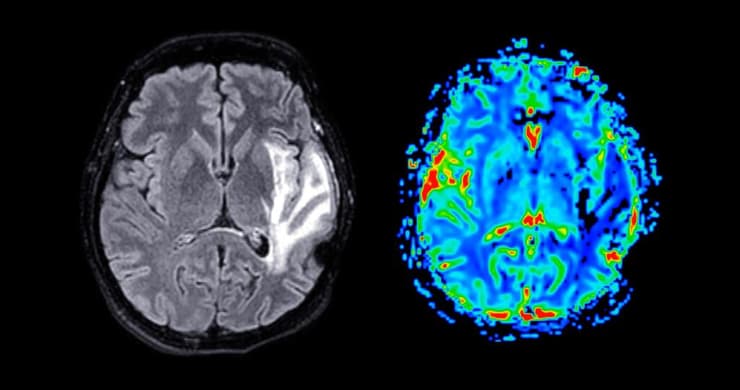

מחלות שגורמות לכאב כרוני כמו פיברומיאלגיה, עייפות כרונית, לונג-קוביד וכד', נחשבות למחלות שקופות, שקשה לאבחן באמצעים המקובלים, מה שמוביל גם לייאוש בקרב החולים בה. אבל ד"ר אונגר דווקא שומר על אופטימיות ומציין שבזכות החדשנות של בית החולים שיבא בתחום, קל יותר להפוך את המחלות האלו לנראות. "אנחנו חוקרים את המחלות האלו בהרבה דרכים, גם על ידי הדמיה, כי המחלה לא באמת שקופה ברמה הגופנית. אפשר לראות אותה בבדיקות ולראות את השינויים להם היא גורמת. הסיבים במוח משתנים, מרכיבים בדם משתנים".

נכון. אנחנו רואים את זה קורה כבר בטיפול במחלות כמו אפילפסיה, פרקינסון או מחלות של קישיון שרירים. ככה למשל אנחנו יכולים לטפל בפוקוס אולטרה-סאונד (על קול מוחי ממוקד), שמאפשר לנו לחתוך סיבים במוח בצורה מאוד מדויקת וסלקטיבית ולפתור בעיות כמו רעד וחוסר שליטה בידיים, בעיות שעוד לא נפתרות ע"י טיפול תרופתי. אנחנו עובדים בשיתוף פעולה עם מרכז המחקר C-BIRD (מרכז שיבא לביו-רפואה דיגיטלית) ובזכות הפיתוחים שלהם אנחנו יכולים לאתר מבין טריליון סיבים במוח את הסיב שאחראי לרעד. במקרה כזה, אנחנו לוקחים את המטופל ל-MRI עם קסדה מיוחדת, מכוונים את הקרניים לאותו סיב ומפסיקים את פעילותו באופן לא פולשני, ללא כל חתך!".